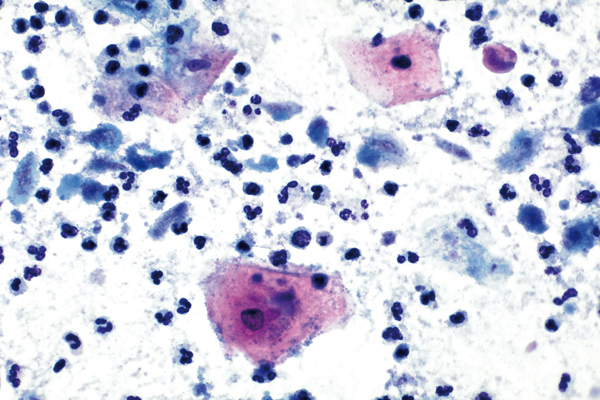

richtige Antwort:

d. Trichomonadenkolpitis (I)

- Vorkommen meist mit bakterieller Mischflora

- Unscheinbare Gebilde mit zyanophilem Zytoplasma

- Angedeuteter Zellkern und rote Körnelung im Zytoplasma

- Starke entzündlich degenerative Begleitreaktion